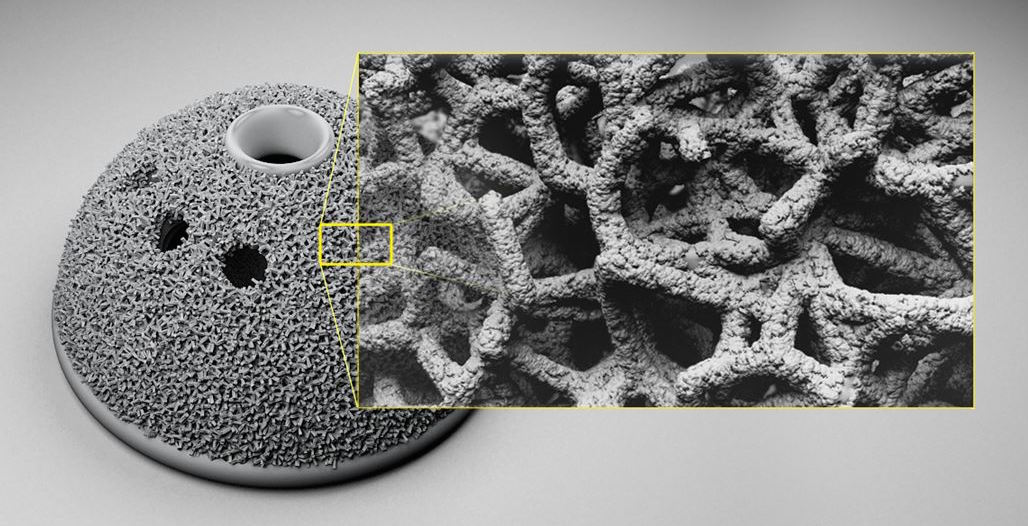

Autodesk Wthin Medical For 3D Printing - 3D Printing Industry

3dprintingindustry.com

3dprintingindustry.com

3d medical autodesk printing implant software printed structure within hip micro risk afraid orthopedic procedures today generative impression opportunity releases